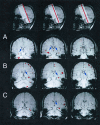

Fig. 2. Brain regions showing a significant, positive correlation between their fMRI signals and the number of successfully encoded words. Colored voxels exceeded the statistical threshold (<0.05) and were overlaid on structural images. In thetop row the red bar depicts the approximate location of structural and functional images in the column below. The bottom three rows depict adjacent slices from three subjects (A–C), with one row corresponding to one individual. The left side of each scan is the right side of the brain. The arrows indicate voxels with significant, positive correlations in the posterior part of the hippocampus.